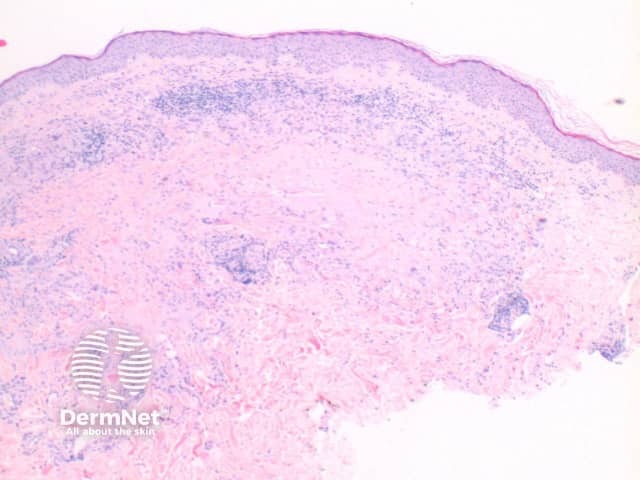

The histological features of granuloma annulare are:

Pathology of granuloma annulare

path gannulare fig 3